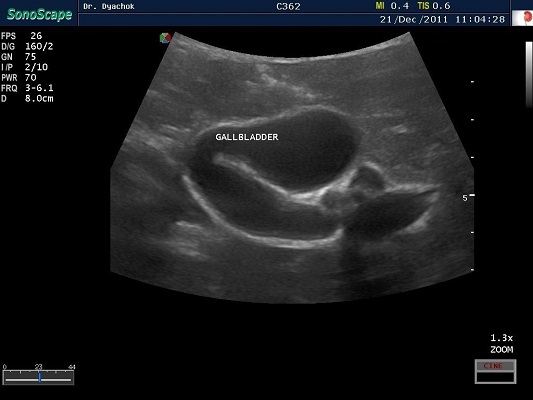

SonoScape S2N Vet – уникальная узи-система, выполненная в виде портативного ноутбука для легкой переноски. Отличается эта система цветным форматом визуализации, а также крайне чувствительными доплеровскими режимами, работающими на уровне премиальных аппаратов. При оптимальной цене – это очень хорошее и сбалансированное решение для ветеринарной клиники.

Диагональ монитора составляет 15,6 дюймов, что обеспечит комфортную работу для врачей и полный спектр визуализации для пациентов. Компактный вес не превышает 5 кг. (вместе с батареей), что оценят выездные бригады скорой помощи или ветеринары, выезжающие на дом.

Цифровая рабочая станция S2N Vet предполагает наличие жесткого диска для записи данных, составление и экспорт отчетов с возможностью добавления изображений, ведение базы данных пациентов.

Данный аппарат является незаменимым помощником в диагностической медицине. Ему нет конкурентов по оснащению, компактности и цене, а значит пора сделать правильный выбор для вашей клиники.